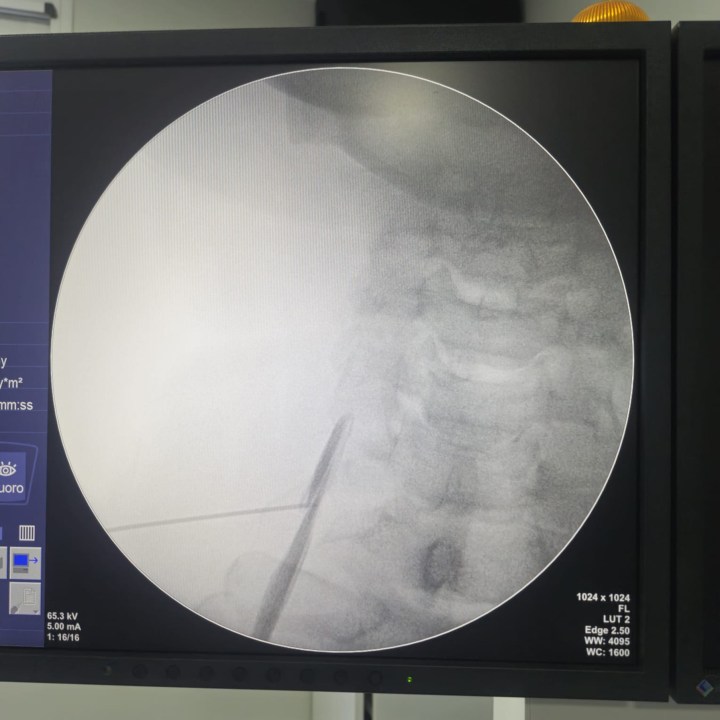

El paciente, de 62 años de edad, viajó más de 320 kilómetros para someterse a una «Neurólisis del ganglio estrellado», que forma parte de la cadena simpática cervical y de esta manera atacar el epicentro del dolor. Esta terapia, con radiofrecuencia, innovadora, le produjo un alivio considerable de su dolencia.

Es la primera vez en la provincia de Río Negro que se utiliza esta técnica híbrida en una institución privada (ecografía más radioscopia) y la primera neurolisis por radiofrecuencia, según aseguró a RIO NEGRO, el especialista Hermosilla.

«Está es la primera que se realiza en una institución privada utilizando una técnica en que se busca garantizar la seguridad del paciente disminuyendo los riesgos, con la certeza de llegar al objetivo a trata con ayuda de la utilización conjunta de la ecografía y la radioscopia».

El «Arco en C» es uno de los aparatos de vanguardia que se utilizan para realizar la terapia. «Ayuda a guiar la aguja para llegar al objetivo a tratar», agregó el médico.